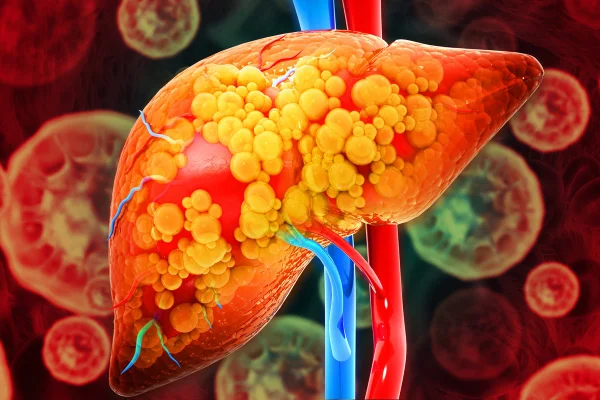

A esteatose hepática é popularmente conhecida como gordura no fígado

Mohammed Haneefa Nizamudeen/Getty Images 2 de 4

A condição de gordura no fígado acomete 30% da população mundial

Magicmine/Getty Images 3 de 4